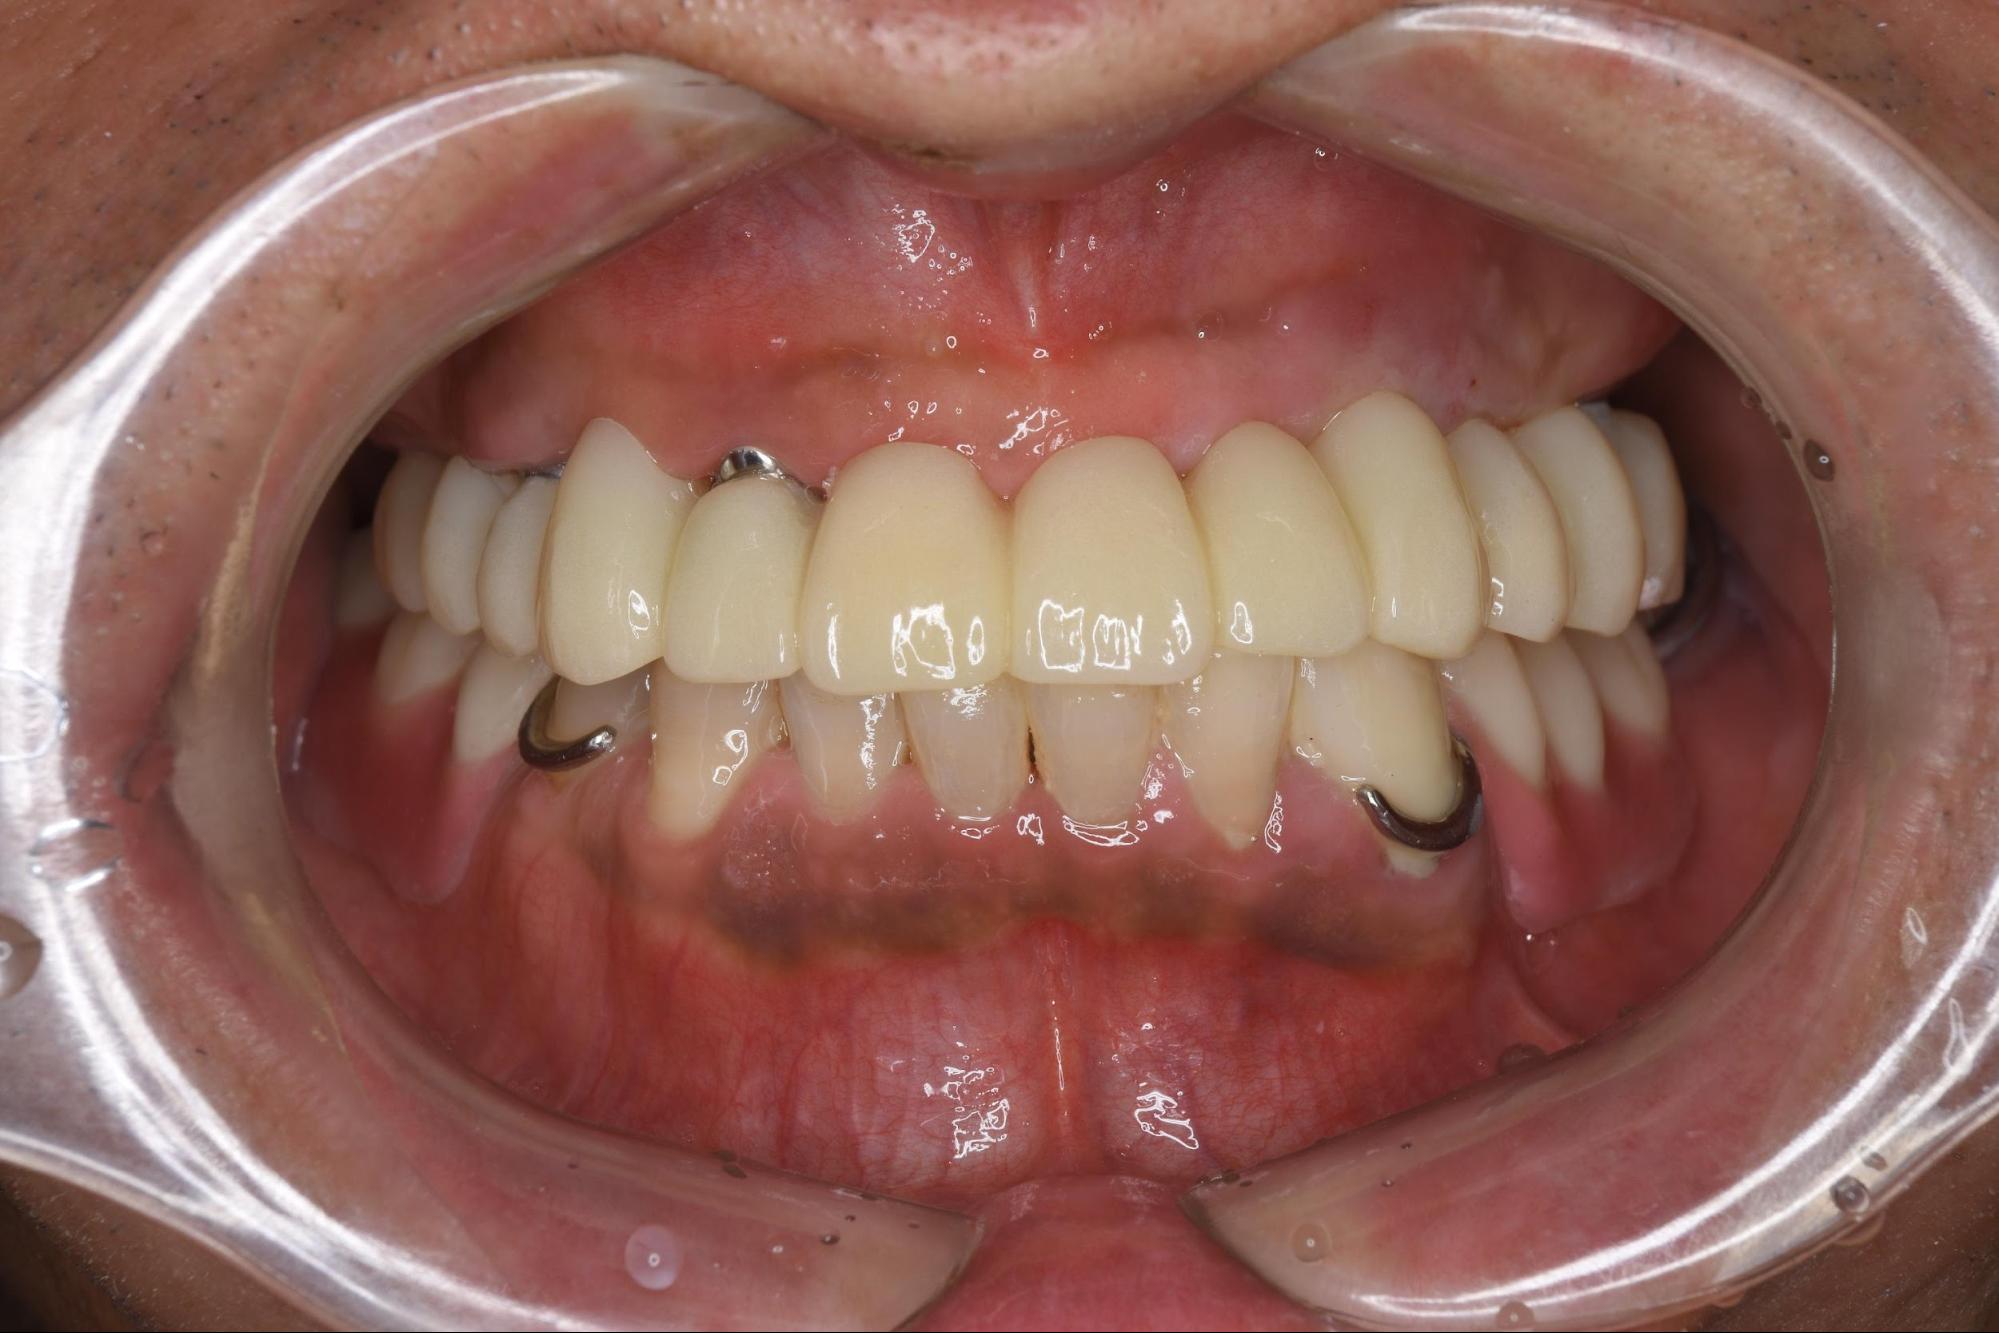

ステップ4:固定式の仮歯(プロビジョナル)の装着

骨との結合を確認した後、いよいよインプラント用の「仮歯」を装着しました。 この仮歯は、今までの仮入れ歯とは異なり、インプラントに直接ネジで固定する「固定式」のものです。 この時点で、何を食べても外れる心配がなくなり、患者さんの食生活は劇的に改善します。

ステップ4画像

ステップ5:最終的な歯(セラミック冠)の製作

この固定式の仮歯には、最終的な歯を成功させるための重要な役割があります。しっかりと噛めるようになることで、噛む力(咬合力)が回復し、顎の動きや噛み合わせも微妙に変化します。 この仮歯を数ヶ月間使用していただきながら、発音や見た目、清掃性、噛み心地などを細かく微調整し、患者さんにとって最適な状態を探っていきます。 この情報を基に、最終的な「セラミック冠(上部構造)」を精密に製作します。

5. 治療後・予後

最終的なセラミックの歯を装着し、治療は完了しました。 (※ここに治療前後の口腔内写真が入る想定です)

取り外し式の入れ歯ではなく、ご自身の歯のようにしっかりと固定された、審美的な歯並びが回復しました。